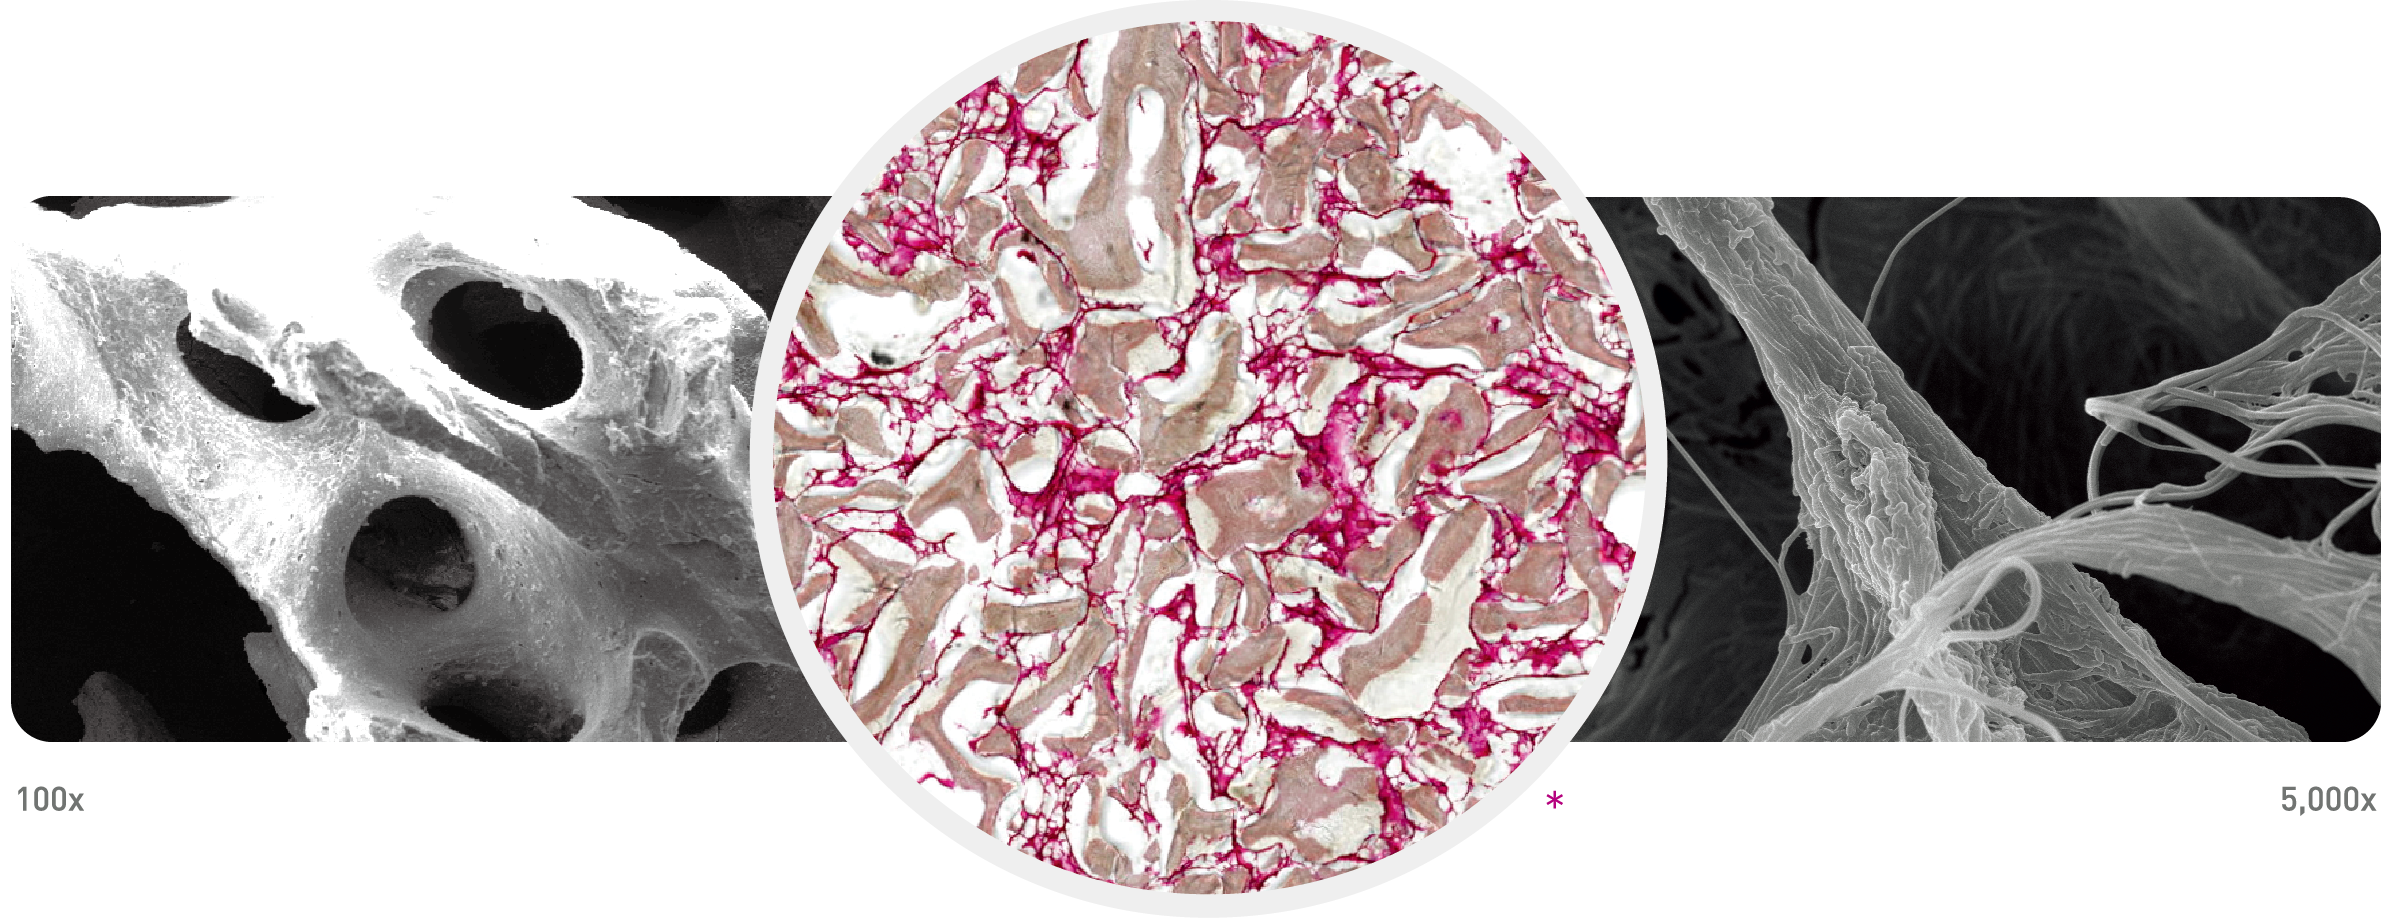

THE Graft™ Collagen block is composed of porcine-derived bone mineral matrix from cancellous bone and atelocollagen from the porcine tendon. THE Graft™ Collagen is a collagenated bone block designed for filling of extraction sockets to enhance preservation of the alveolar ridge.

THE Graft™ Collagen bone mineral matrix is similar to physical and chemical aspects of human bone mineralized matrix. Hydrated collagen components have a viscosity that facilitates for blending of bone mineral matrix.

With this characterization, THE Graft™ Collagen can be trimmed and/or molded to various defect shapes and can be fixed in bone defect sites. As time passes, THE Graft™ Collagen is partially remodeled by the osteoclast and osteoblast cells.

THE Graft™ (porcine-derived Xenograft) + Type I Collagen

Optimal osteoconductivity

While retaining better handling properties, THE Graft™ Collagen is able to

form sufficient osseous tissue for implant placement and maintain natural

volume and great adhesion property which lead to minimum chair time.

Predictable clinical results

With great hydrophilicity, THE Graft™ Collagen stabilizes the clot and aids in

revascularization of the grafting material in the defect area to increase cell

migration efficiency to the minreal substrate. As a result, fast bone formation

can be expected, as well as a predictable clinical result.